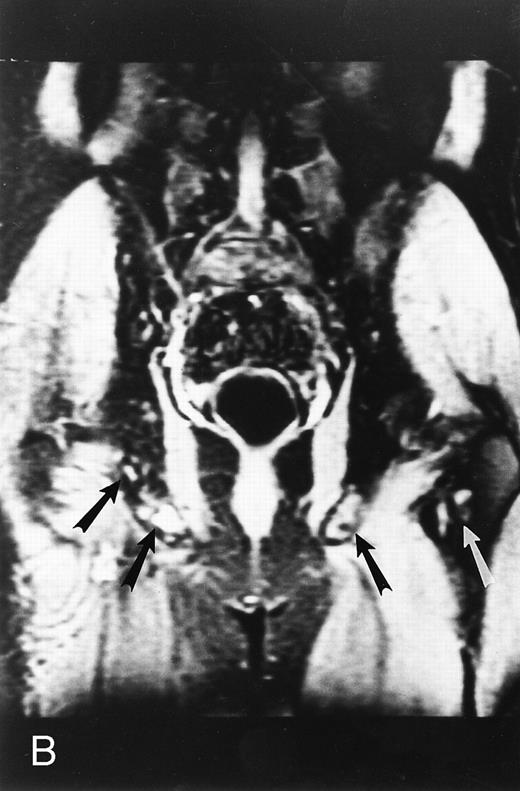

A 75-year-old woman with Waldenstrom macroglobulinemia: T1-weighted (600/20, TR/TE) axial (A) and sagittal T1-weighted (600/20, TR/TE) precontrast (B) and postcontrast (C) MR images of the lumbosacral spine. Note diffuse pattern of marrow infiltration and enlarged retroperitoneal lymph nodes (arrows). The abnormal marrow is isointense to the intervertebral discs on the precontrast image and enhances markedly becoming hyperintense to the discs on the postcontrast image.

A statistically significant relationship was shown between grades of contrast uptake by the abnormal marrow on enhanced MR images and values of hemoglobin and lymphoplasmacytoid infiltration indices of the bone marrow.38 Increasing grades of contrast uptake on enhanced MR images correlated with increasing tumor burden. A direct correlation was found between decreased enhancement of the marrow on posttreatment MR images and degree of clinical response.38 The application of quantitative analysis of the involvement of the marrow on MR images to the assessment of response to therapy in patients with macroglobulinemia may be of value in individual problem cases.